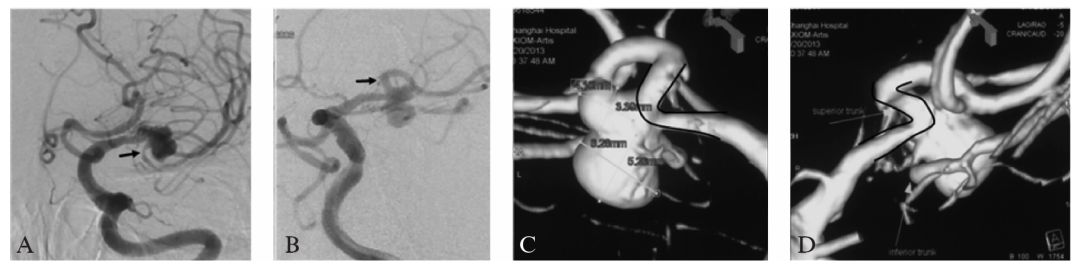

DSA:左侧颈内动脉造影显示左侧大脑中动脉分叉部相对宽颈动脉瘤,动脉瘤呈分叶状,且同时累及上干和下干(图10-2A、B);三维旋转造影重建显示载瘤动脉在瘤颈处成约60°的锐角,主要累及上干,下干自瘤颈处发出。标记测量:动脉瘤最大径约9.7 mm,瘤颈约2.8 mm,两分叶小泡大小分别为6.28 mmX5.26 mm,4.1 mmX3.39 mm,载瘤动脉近远端直径分别为2.03 mm及1. 65 mm(图10-2C、D)。

图10-2 患者术前DSA及三维重建影像

A,B:工作角度造影显示左侧大脑中动脉分叉部宽颈动脉瘤.动脉瘤呈分叶状,且同时累及上干和下干;

C:三维旋转造影重建显示M2,M3在瘤颈处成明显约60°的锐角,下干自瘤颈处发出